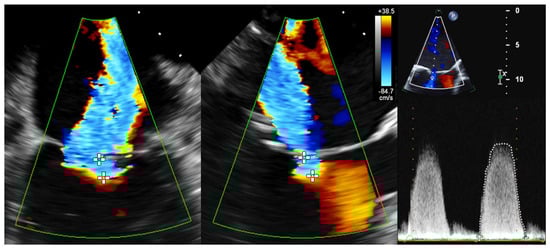

To determine the EROA using 2D PISA, biplane 2D color Doppler images (X-Plane views) were acquired optimally at a Nyquist velocity between 20 and 45 m/s. In the TEE 4-chamber view as well as in the orthogonal section plane with maximal expression of proximal convergence, the radius of proximal convergence between color change and plane of coaptation defect (minimal regurgitation area) was measured in mid-systole over different heartbeats. In addition, the maximum regurgitation velocity (MR-Vmax) and velocity–time integral (MR-VTI) in systolic phase of CW Doppler recordings were determined (Figure 2). Using the PISA method, the EROA was calculated according to the recommendations of the European Association of Cardiovascular Imaging (EACVI) [2].

Figure 2. Determination of 2D PISA in biplane 2D color Doppler dataset and CW Doppler dataset. Echocardiographic images with 2 orthogonal slice planes of the 2D color Doppler dataset (mid-systolic) with Nyquist velocity of 38.5 cm/s (left); determination of PISA radius in 2 planes (diameters with crosses), MR-VTI (dotted outline), and MR-Vmax in the CW Doppler dataset (right) for calculation of regurgitation area. Abbreviations: 2D = two-dimensional; PISA = proximal isovelocity surface area; CW = continuous wave; MR-VTI = mitral regurgitation velocity–time integral; MR-Vmax = maximum mitral regurgitation velocity.